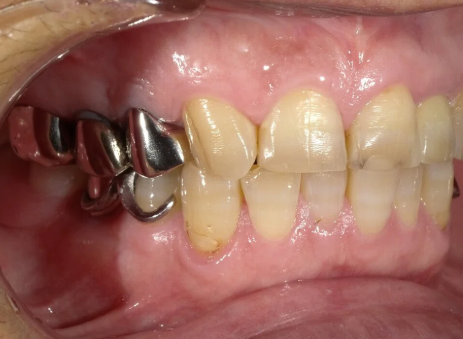

e.max クラウン

BEFORE

AFTER

年齢:50代女性

治療内容:左上真ん中から2番目の歯で、他院様での修復物不適合で見た目を気にされてご相談を受けました。e.maxクラウンの審美修復で、ご自身の歯に近い自然で美しい見た目に仕上がりました。

治療期間/通院回数:3回

費用: e.max クラウン 110,000円 ※2025年7月現在の価格